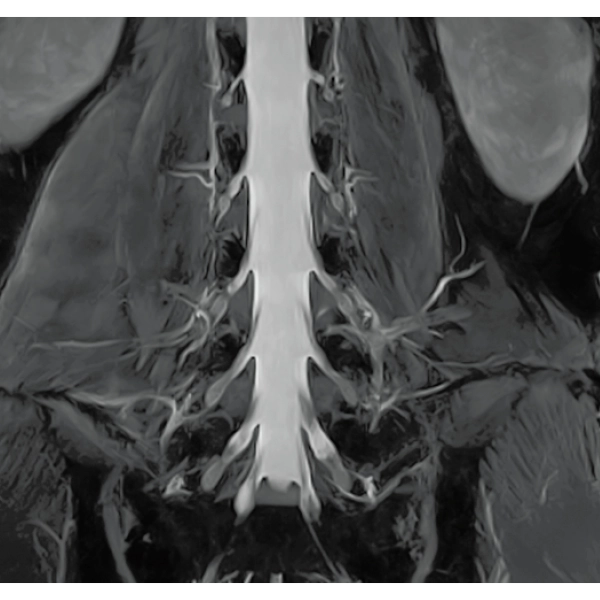

"DLR" is applicable to all body parts and promotes high speed imaging and diagnostic efficiency

IP-RAPID x DLR Plus can also shorten imaging time, allowing more images to be taken in the same examination time.

Additional imaging, such as different image types and cross sections, can be added to the conventional examination to increase the amount of information and make the diagnosis more reliable.

IP-RAPID x DLR Plus can be used for basic imaging such as VolumeScan, RadialScan, HalfScan, and many other imaging methods such as MultiContrastScan FatSep and DWI.

It can also be used with time-consuming scans such as Whole Body DWI and Whole Spine imaging, providing more detailed information in many areas than previously possible.